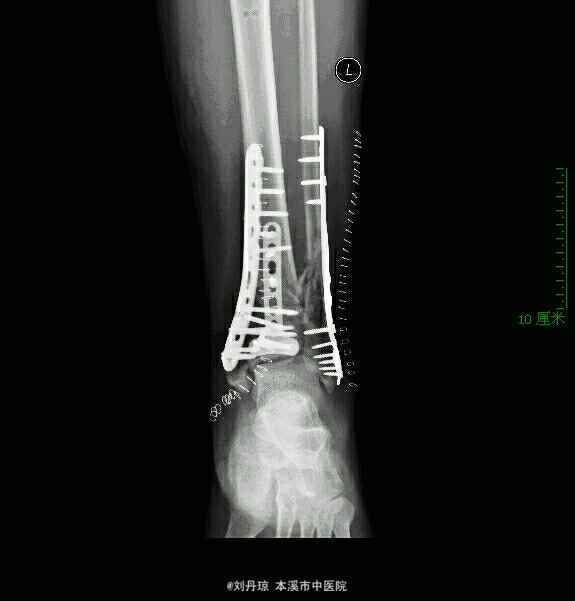

左踝pilon骨折 外固定架复位后取腓骨后缘切口,行腓骨解剖板内固定。取踝关节前内侧入路,在前内侧和前方放置接骨板。

随访2年,手术时机的选择有争议,有人建议维持距骨中立位,7~12天内手术;有人建议急诊手术或12天以后手术,还有人建议急诊行腓骨固定,择期行胫骨固定。本人建议根据软组织情况、骨折严重程度、伤后时间采取不同对策。